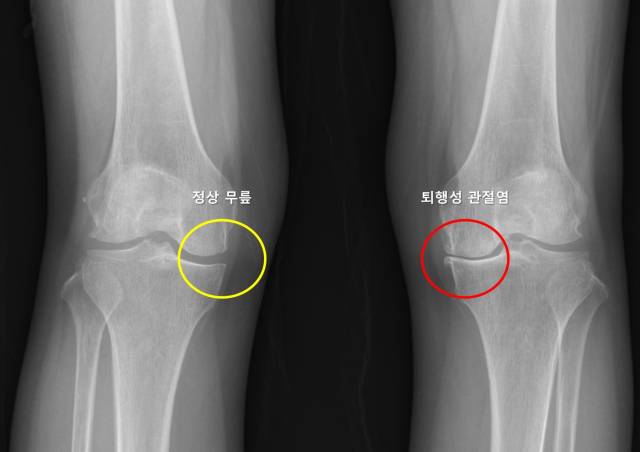

무릎 퇴행성 관절염은 연골의 점진적인 손상과 관절 구조물의 퇴행성 변화로 인해 발생하는 질환이다. 전 세계 인구의 약 16~30%에서 발생할 정도로 흔하지만 통증과 운동 제한을 유발해 삶의 질을 크게 저하시킬 수 있다. 더욱이 고령화 사회로 접어들면서 무릎 퇴행성 관절염의 유병률은 꾸준히 증가하는 추세다. 한쪽 무릎에 관절염이 생긴 뒤 수년 내 반대쪽 무릎에서도 통증이나 구조적 변화를 경험하는 환자들이 많은데, 이를 예측하려는 연구는 부족했다. 이러한 양측성 진행이 모든 환자에게서 동일하게 나타나는 것은 아니라 일반화하기에도 어려움이 많았다.

연구팀은 미국의 대규모 관절염 추적 코호트인 OAI(Osteoarthritis Initiative)와 MOST(Multicenter Osteoarthritis Study) 데이터셋을 기반으로 4~5년간 추적 관찰된 편측 무릎 퇴행성 관절염 환자 1353명을 분석했다. 그 결과 OAI 코호트에서는 172명(19.1%), MOST 코호트에서는 178명(39.3%)이 반대쪽 무릎에서도 퇴행성 관절염이 진행된 것으로 나타났다. 연구팀은 OAI 900명의 데이터를 모델 학습용으로, MOST 453명의 데이터를 검증용으로 삼고 Tree-based Pipeline Optimization Tool 알고리즘을 활용해 머신러닝 기반 예측 모델을 구축했다. 알고리즘은 △성별 △반대쪽 무릎의 외측 관절 간격 감소 △반대쪽 무릎의 반월판 절제술 수술력 △체질량지수(BMI) ▲관절염 무릎의 관절염 정도(KLG) △인종 △반대쪽 무릎의 기존 관절염 정도 △반대쪽 무릎의 통증 및 기능 지표인 WOMAC 점수△관절염 무릎의 WOMAC 점수 등 총 9가지 변수를 기반으로 설계됐다.

SHAP 분석 결과, 예측에 가장 큰 영향을 미친 요인은 성별이었고 반대쪽 무릎의 외측 관절 간격 감소, 반월판 절제술 병력, BMI 등의 순이었다. 특히 반대쪽 무릎의 외측 관절 간격 감소의 위험 비율(odds ratio)이 4.475로 가장 높았고, 반대쪽 무릎 퇴행성 관절염 발생 위험을 약 4.5배 증가시키는 주요 요인으로 확인됐다.

기존 관절염이 있는 무릎의 관절염 정도(KLG)와 통증 및 기능 지표(WOMAC 점수)가 반대쪽 무릎 퇴행성 관절염 발생과 유의미한 연관성을 갖는다는 사실도 이번 연구에서 처음 밝혀졌다. 성별이나 BMI 등 기존에 알려진 일반적 위험 요인 외에 반대쪽 무릎 자체의 구조적 특성이 관절염 발생 예측에 중요한 역할을 하는 것으로 나타났으며, 외측 관절 간격 감소가 핵심 예측 요인으로 확인된 것도 이번 연구의 주요한 성과로 꼽힌다.